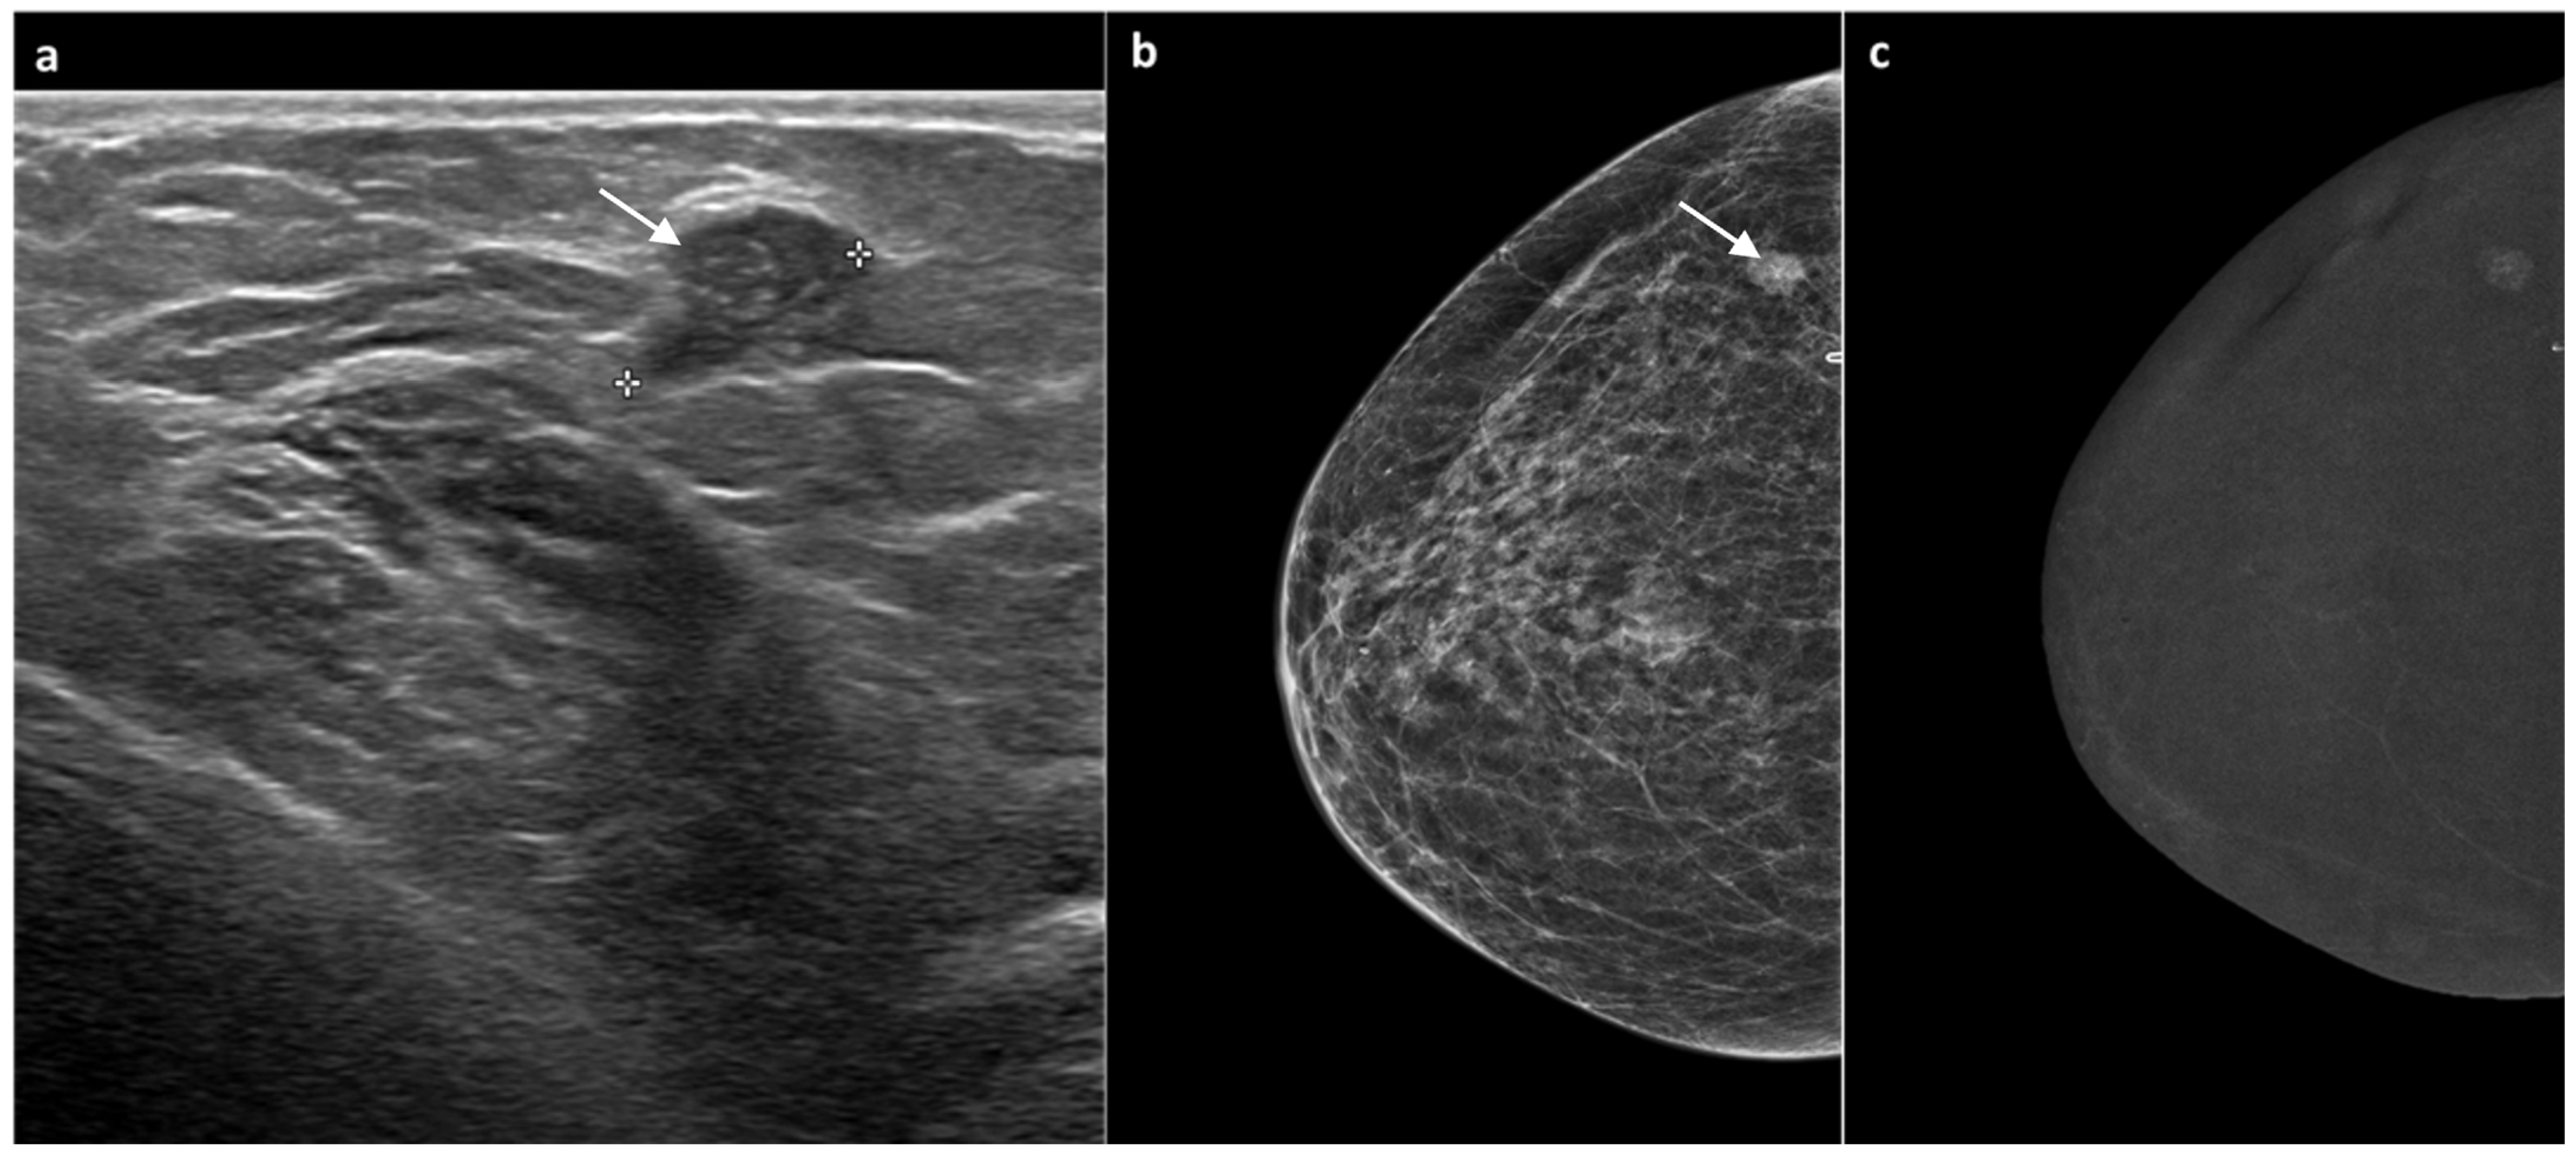

3.2. CEM Examination and Analysis